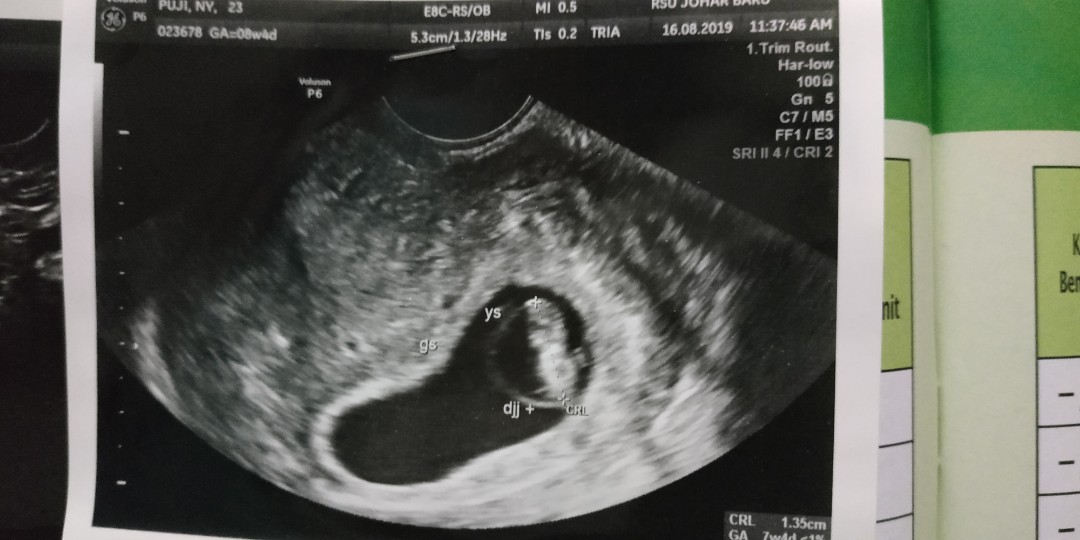

Ini usg aku 7w3d bun..udah ada janin sma detak jantung nya